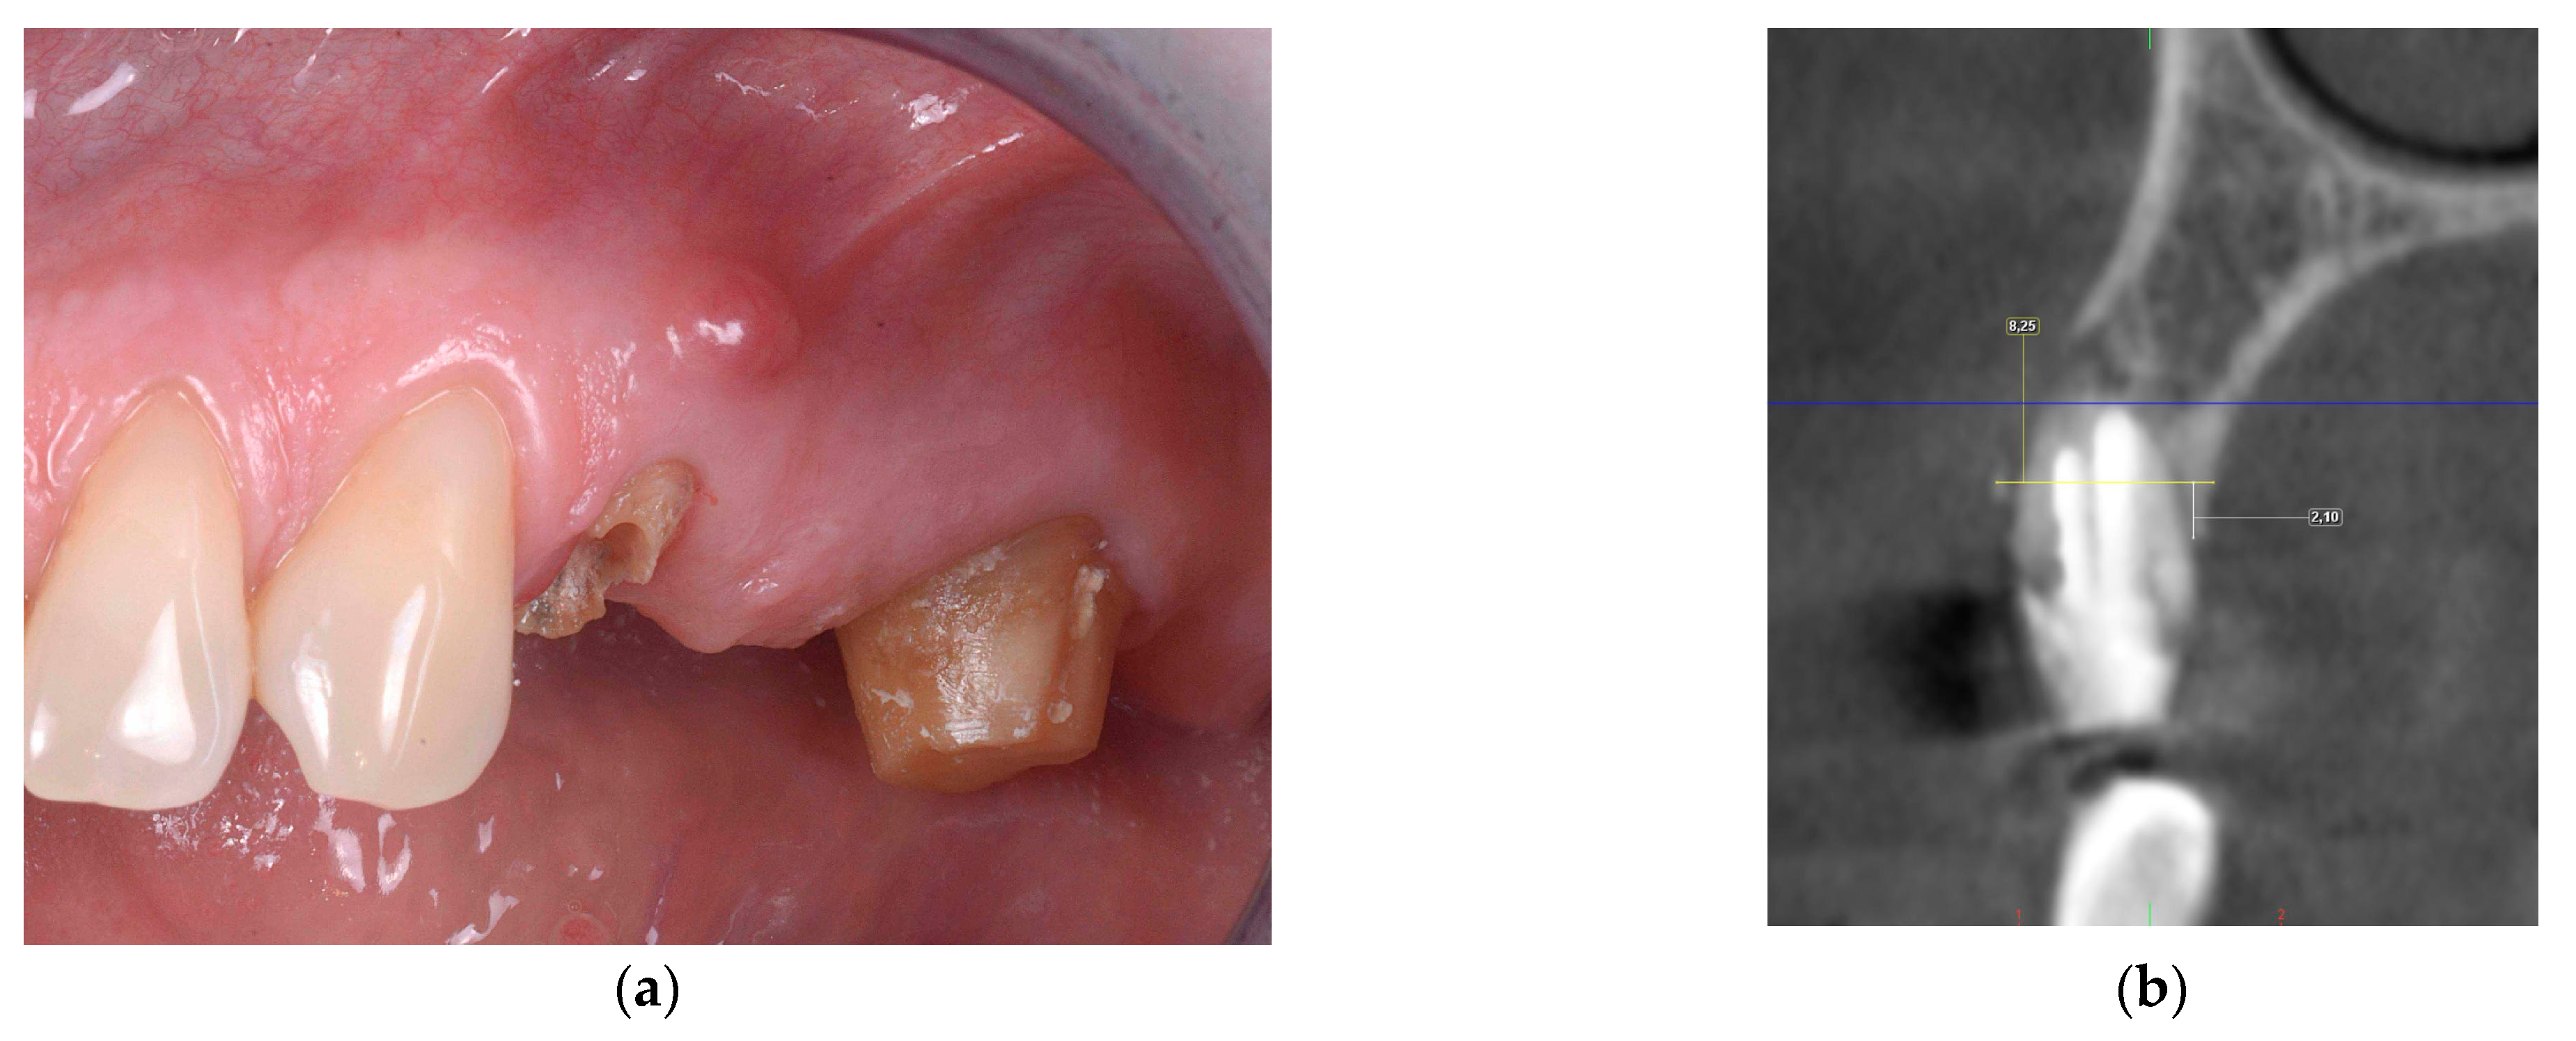

2.2.1. Horizontal and Vertical GBR Using F.I.R.S.T.

2.2.2. Immediate Implant Placement Using F.I.R.S.T.

2.2.3. ARP and Delayed Implant Placement Using F.I.R.S.T.

- Foti, V.; Rossi, R. Fibrinogen-induced regeneration sealing technique (first) an improvement and modification of traditional gbr: A report of two cases. Mod. Res. Dent. 2020, 5, 476–485. [Google Scholar]

- Foti, V.; Savio, D.; Rossi, R. One-time cortical lamina: A new technique for horizontal ridge augmentation. A Case Ser. Br. J. Healthc. Med. Res. 2021, 8, 22–30. [Google Scholar] [CrossRef]

- Foti, V. Fibrinogen-induced regeneration sealing technique (f.I.R.S.T.). In Building Better Bone: A Comprehensive Guide to gbr Techniques; Rossi, R., Ed.; Quintessence Publishing: Batavia, IL, USA, 2024; pp. 210–227. [Google Scholar]

- Faro, L.L.; Strappa, E.M.; Carù, F.G.; Nanni, M.; Invernizzi, M.; Testori, T. Rigenerazione ossea guidata con tecnica first (fibrin-induced regeneration sealing technique). Case report con evidenze istologiche. Quintessenza Internazionale Riv. Di Odontoiatr. 2023, 37, 10–21. [Google Scholar]